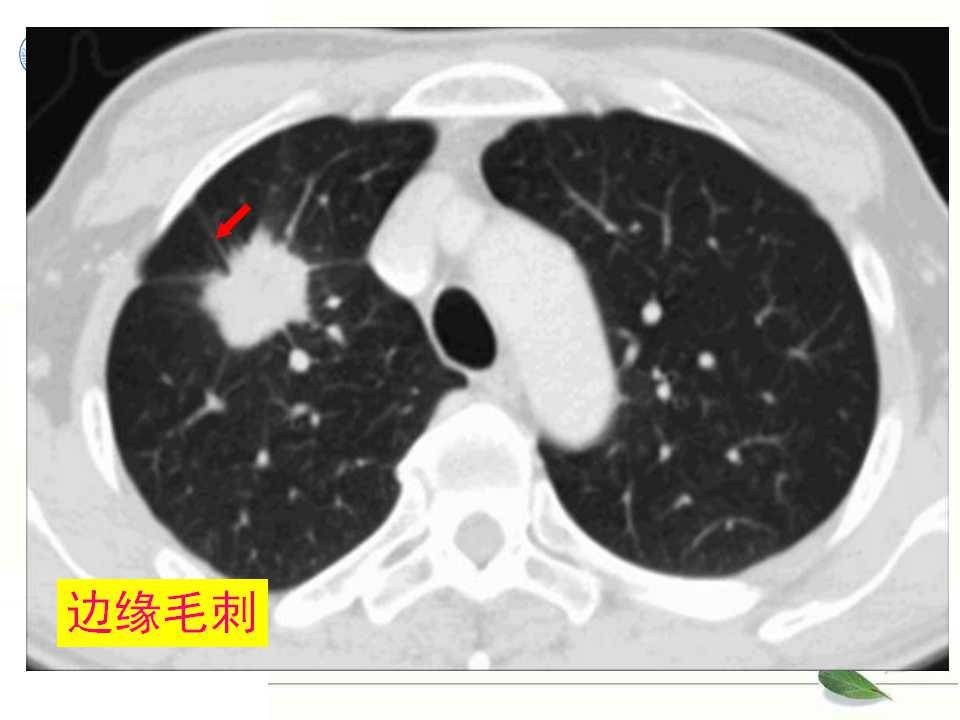

肺癌的影像学检查